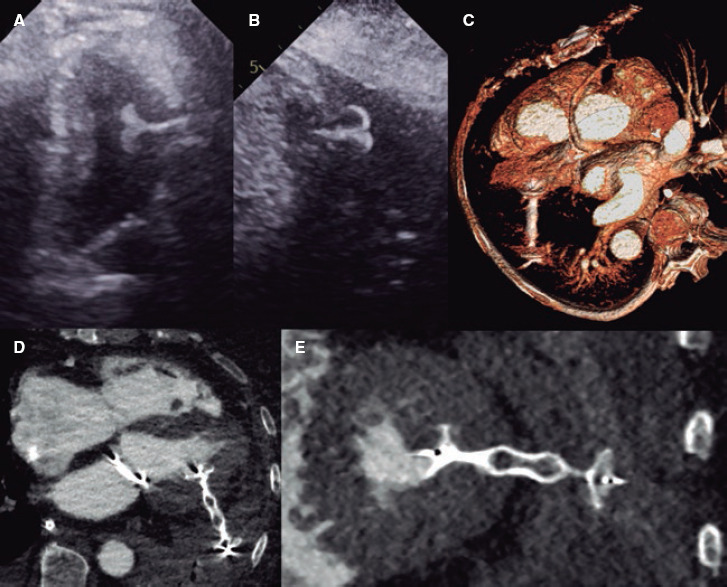

Percutaneous closure of left ventricular puncture after thoracentesis.